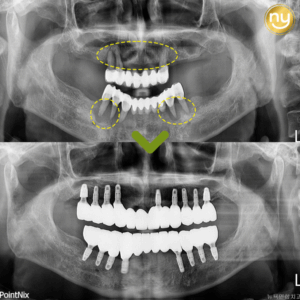

울산삼산치과 전악임플란트를 고민중이라면 안녕하세요. 울산삼산치과 뉴욕연합치과입니다. 유치는 탈락하고 난 후 영구치가 자라지만 영구치는 손상되거나 탈락 시 새로운 치아가 자라거나 손상된 부분이 회복되지 않기 때문에 조기에 예방과 관리를 하여 치아를…